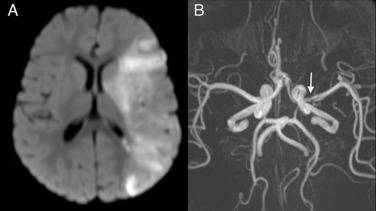

Il bambino, infettato dal virus, ha avuto un ictus.

La madre lo ha portato al pronto soccorso quando ha notato che la sua gamba destra e il braccio fossero deboli. I medici si sono accorti che faticava a muovere una parte del viso, sintomo di un ictus.

“Tutti pensano che si tratti di una malattia leggera, ma ci sono invece una serie di gravi complicazioni. In pratica la varicella attacca i larghi vasi sanguigni nel cervello causando un’infiammazione. Si può creare una mancanza di flusso sanguigno al cervello che può portare a un ictus” spiega la Dottoressa Tina Tan, dell’Accademia Americana di Pediatria.

Il bambino è sopravvissuto ma è molto probabile che abbia delle conseguenze di carattere neurologico o addirittura un altro ictus.